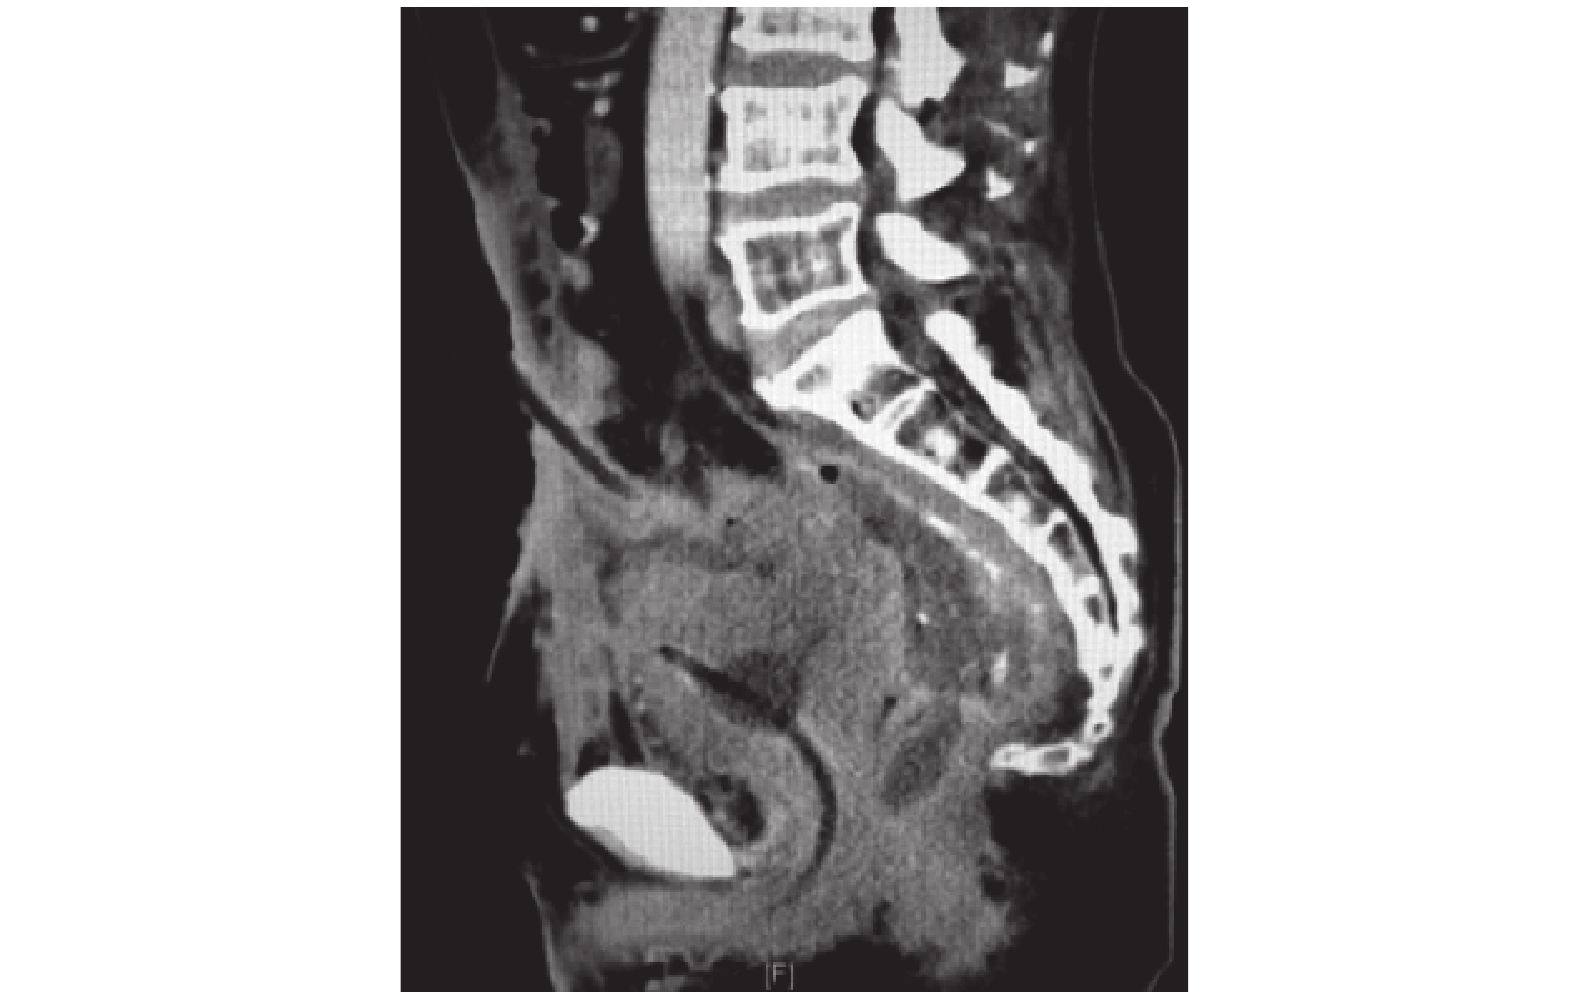

病例 3,病史較長,有下腹部隱痛合并尿路感染,CT 及腸鏡檢查見乙狀結腸及降結腸多發憩室(圖 3a),PET-CT 提示乙狀結腸-膀胱及乙狀結腸-直腸間多發條索樣含氣代謝增高灶,乙狀結腸壁多發代謝增高灶,傾向瘺管合并炎癥可能性大。消化道造影提示乙狀結腸憩室炎、憩室穿孔伴竇道形成(圖 3b),但尿路造影見膀胱充盈良好。考慮結腸憩室穿孔形成慢性炎性粘連,最終導致結腸膀胱瘺。